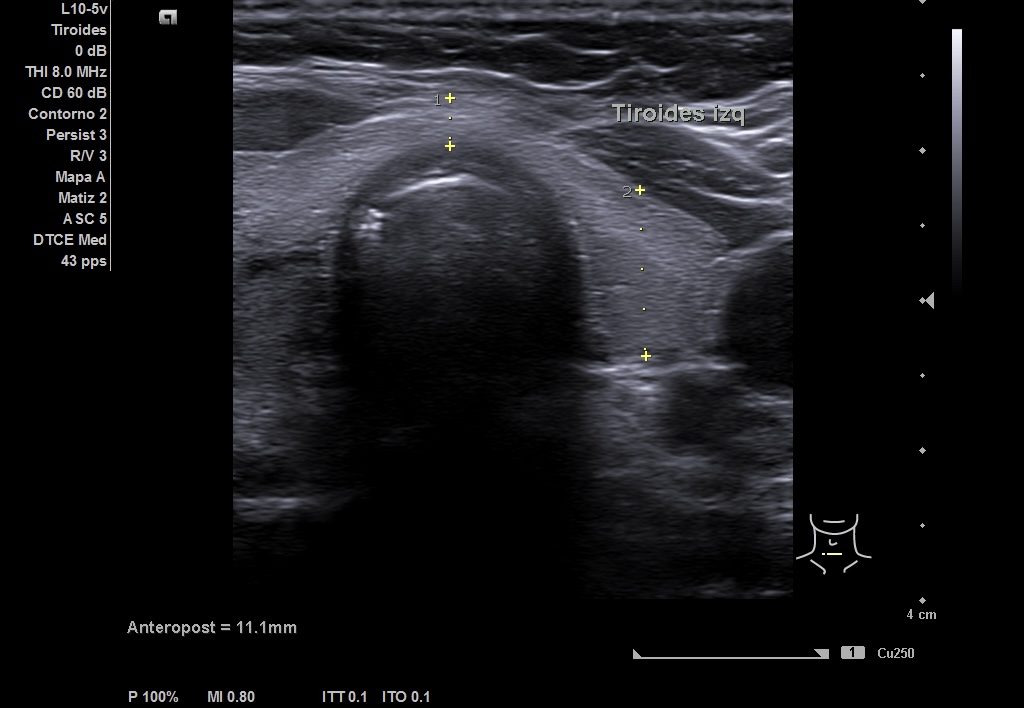

Se realiza ecografía en el Centro de Salud, en la que se objetiva en LTD un nódulo que impresiona de bilobulado, sólido, con una región caudal calcificada que no deja valorar su contenido y una parte superior isoecoica con alguna zona más hipoecoica. Diámetro antero-posterior (13 mm) mayor que el transversal (8 mm) y sagital (19 mm). Vascularización periférica. TIRADS 4-5.